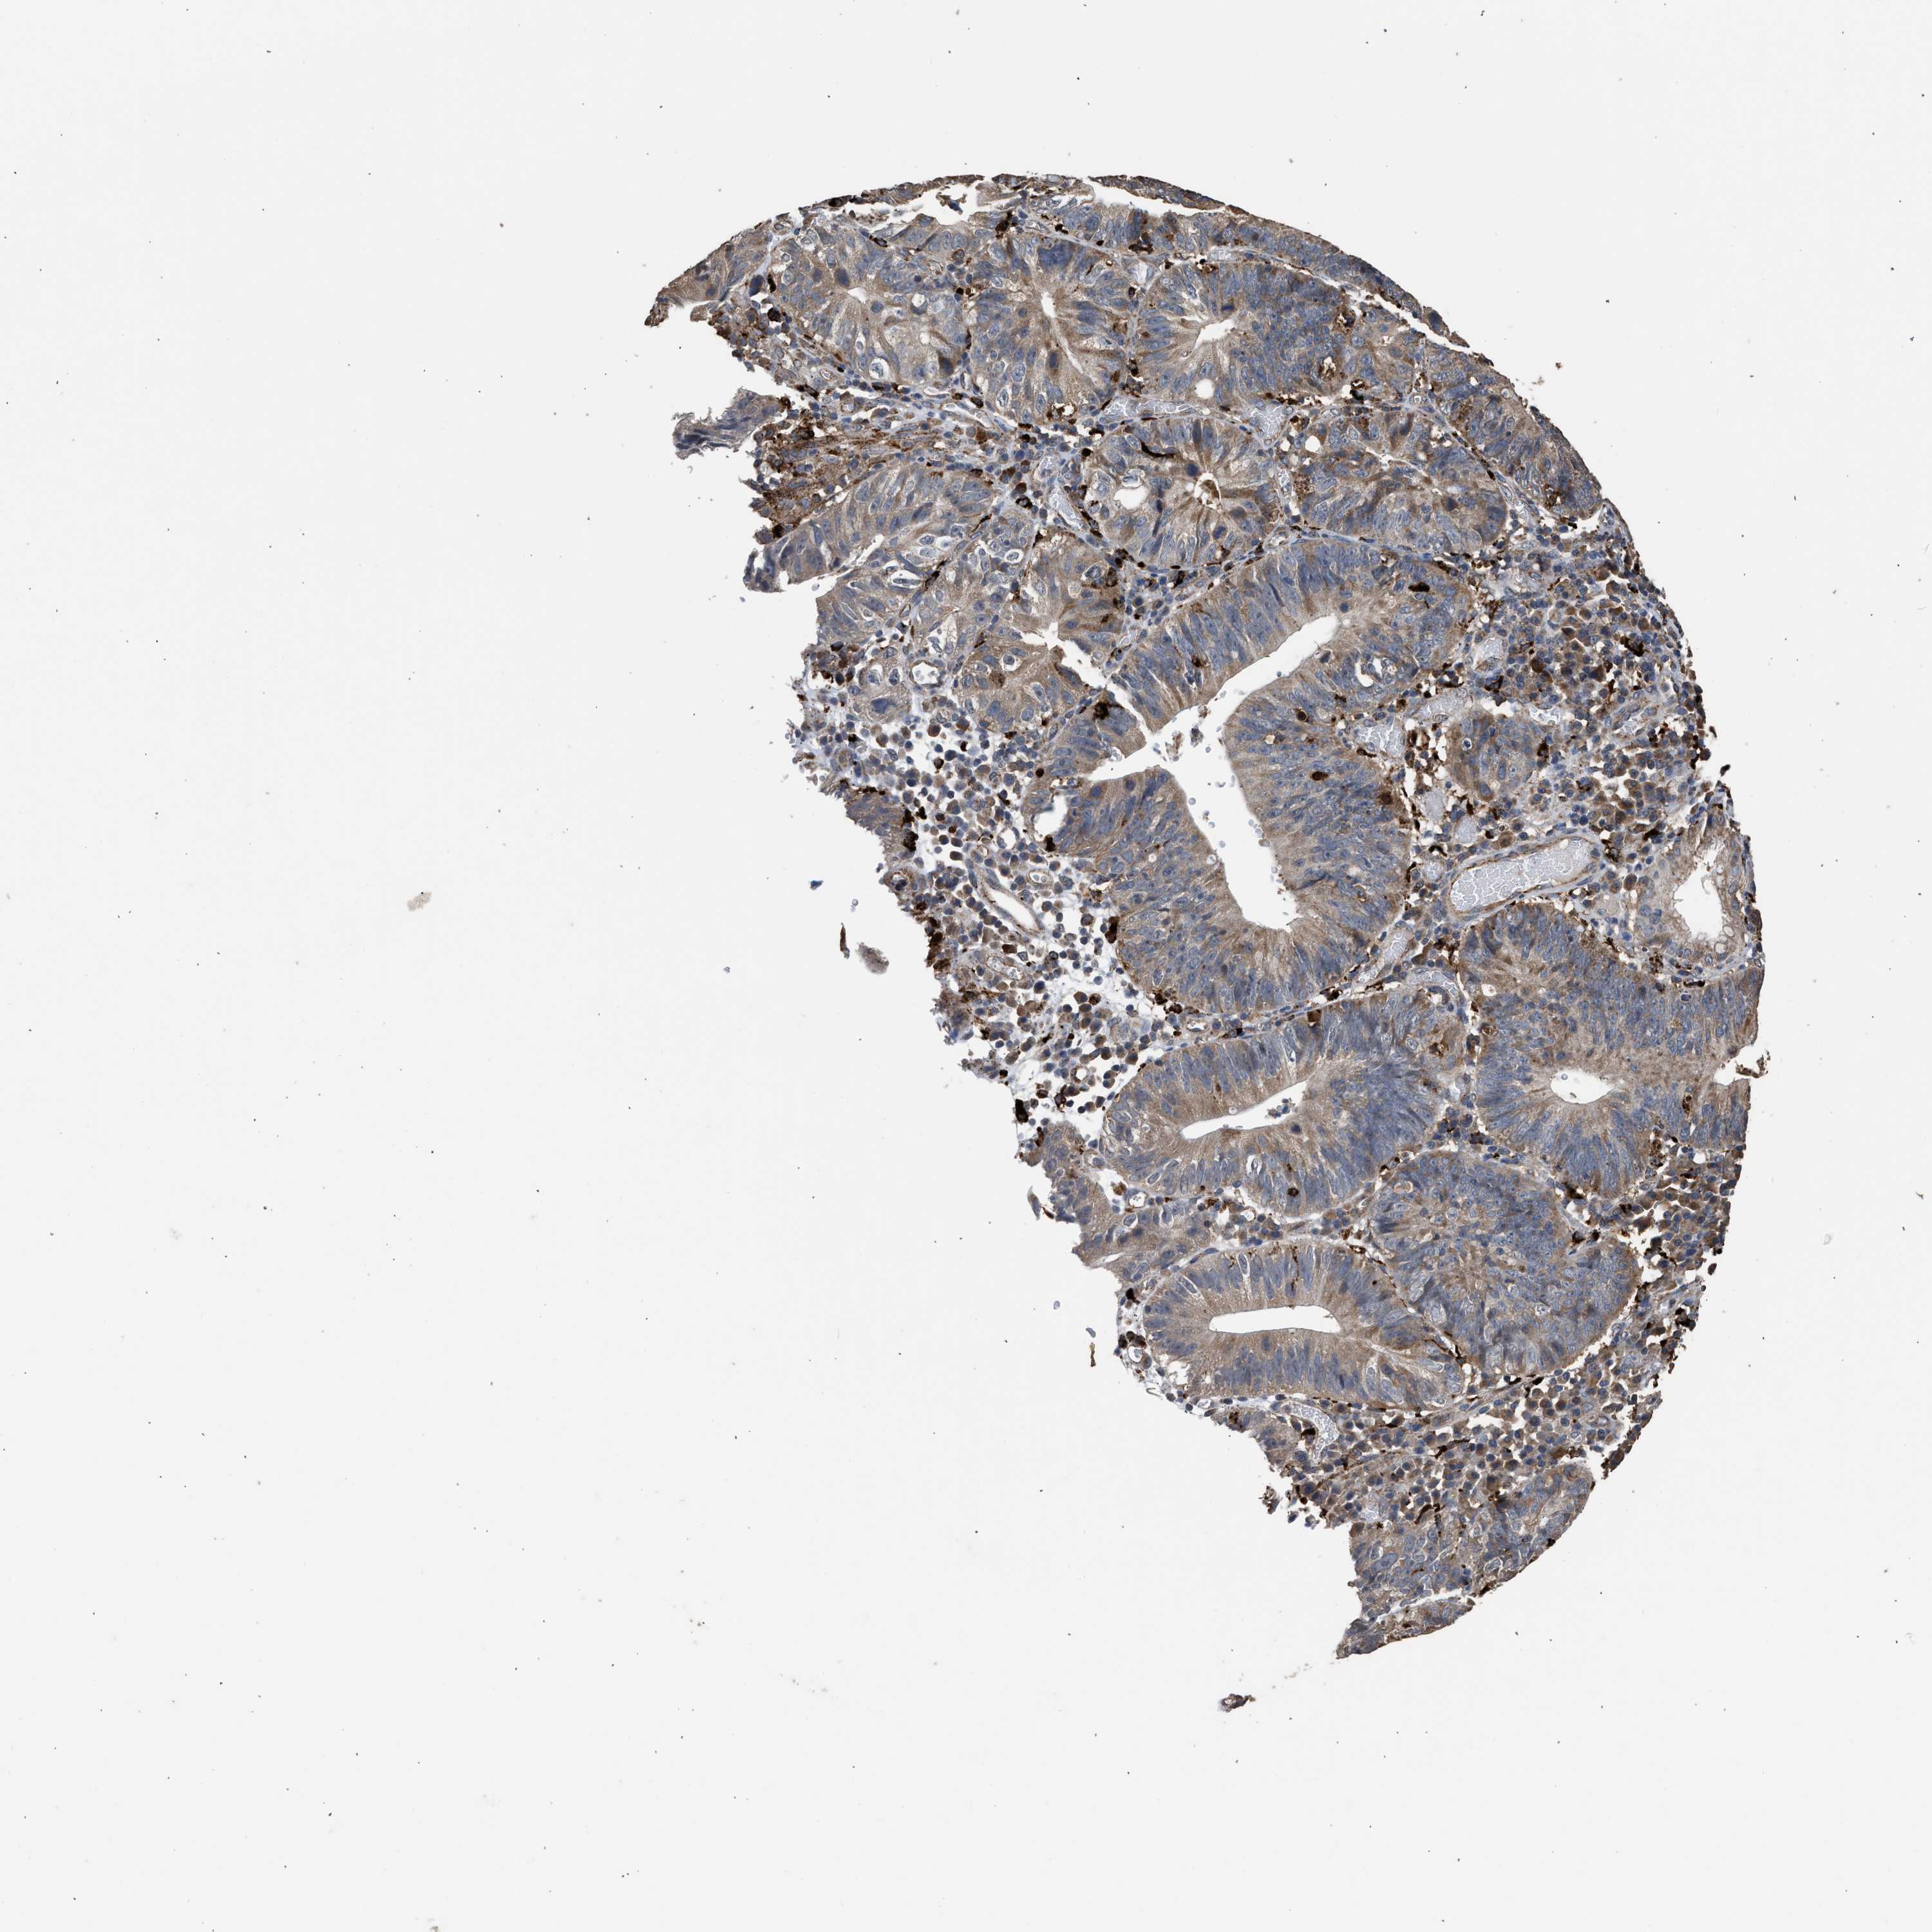

STOMACH CANCER - Protein expressioni

A mouse-over function shows sample information and annotation data. Click on an image to view it in a full screen mode. Samples can be filtered based on level of antibody staining by selecting one or several of the following categories: high, medium, low and not detected. The assay and annotation is described here.

Note that samples used for immunohistochemistry by the Human Protein Atlas do not correspond to samples in the TCGA dataset.

Antibody stainingi

Antibody staining in the annotated cell types in the current human tissue is reported as not detected, low, medium, or high, based on conventional immunohistochemistry profiling in selected tissues. This score is based on the combination of the staining intensity and fraction of stained cells.

Each image is clickable and will lead to virtual microscopy that enables deeper exploration of all samples and also displays staining intensity scores, fraction scores and subcellular localization as well as patient and tissue information for each sample.

Antibody CAB017112

Staining

High

Medium

Low

Not detected

Intensity

Strong

Moderate

Weak

Negative

Quantity

>75%

75%-25%

<25%

None

Location

Nuclear

Cytoplasmic/membranous

Cytoplasmic/membranous,nuclear

Adenocarcinoma, NOS

Adenocarcinoma, High grade